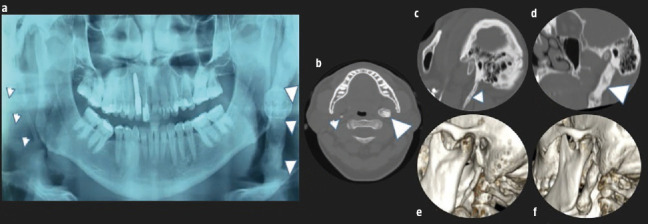

A 55-year-old man presenting with headache, difficulty to opening the mouth and pain on palpation of the left masseter muscle for six months, and left peripheral facial palsy in the last month. Radiography and computed tomography (Fig. 1) showed enlarged styloid processes, compatible with Eagle´s syndrome. After excision of the left styloid process (Fig. 2) the patient was cured.

Panoramic pain radiograph showing enlarged styloid processes (arrowheads), with coarse appearance and pseudoarthrosis on the left (a). Computed tomography in axial (b) and oblique sagittal planes (c and d) and 3D volume rendering reconstructions (e and f). Enlarged styloid processes (arrowheads), with coarse appearance and pseudoarthrosis on the left.